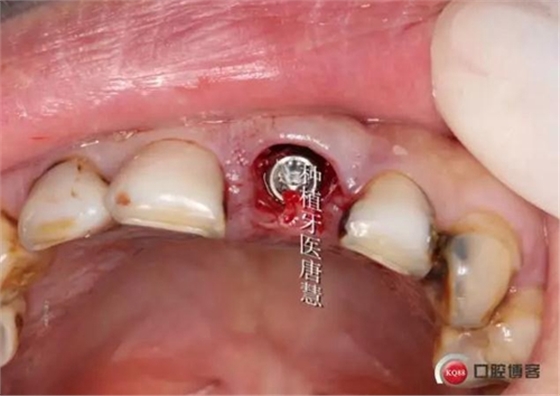

植入植體

植體位于腭側(cè)骨緣下1mm